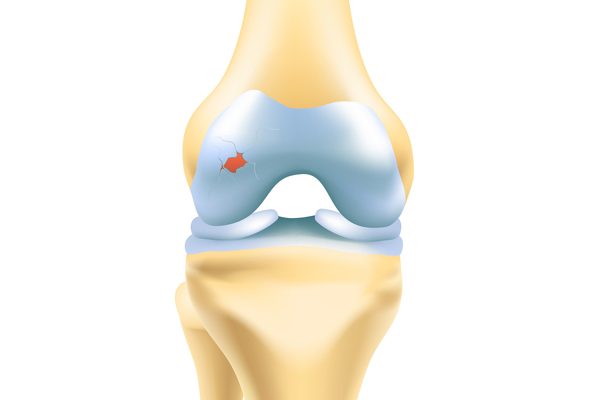

Articular Cartilage

Knee Treatments